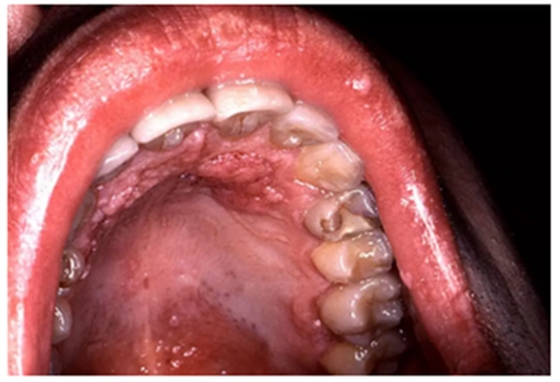

當(dāng)口腔變成白色、褐色或黑色,尤其是口腔黏膜變粗糙、變厚或呈硬結(jié),意味著黏膜表皮細(xì)胞發(fā)生了變化。出現(xiàn)口腔黏膜白斑、紅斑時(shí),很可能意味著口腔細(xì)胞已發(fā)生癌變。

1、口腔內(nèi)出現(xiàn)紅色、白色斑點(diǎn)